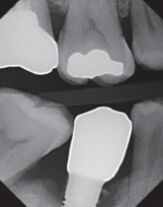

18.右側下顎第一大臼齒接受植牙治療,於牙冠黏著固定3個月後,追蹤檢查無咬合異常,但植牙區明顯有牙齦出血及流膿,檢測囊袋深度>5 mm,根尖X光片如圖所示。造成其植體周圍炎最可能的原因為何? (A)不當咬合力 (B)假牙邊緣不密合 (C)黏著劑殘留 (D)後牙向前傾斜分力